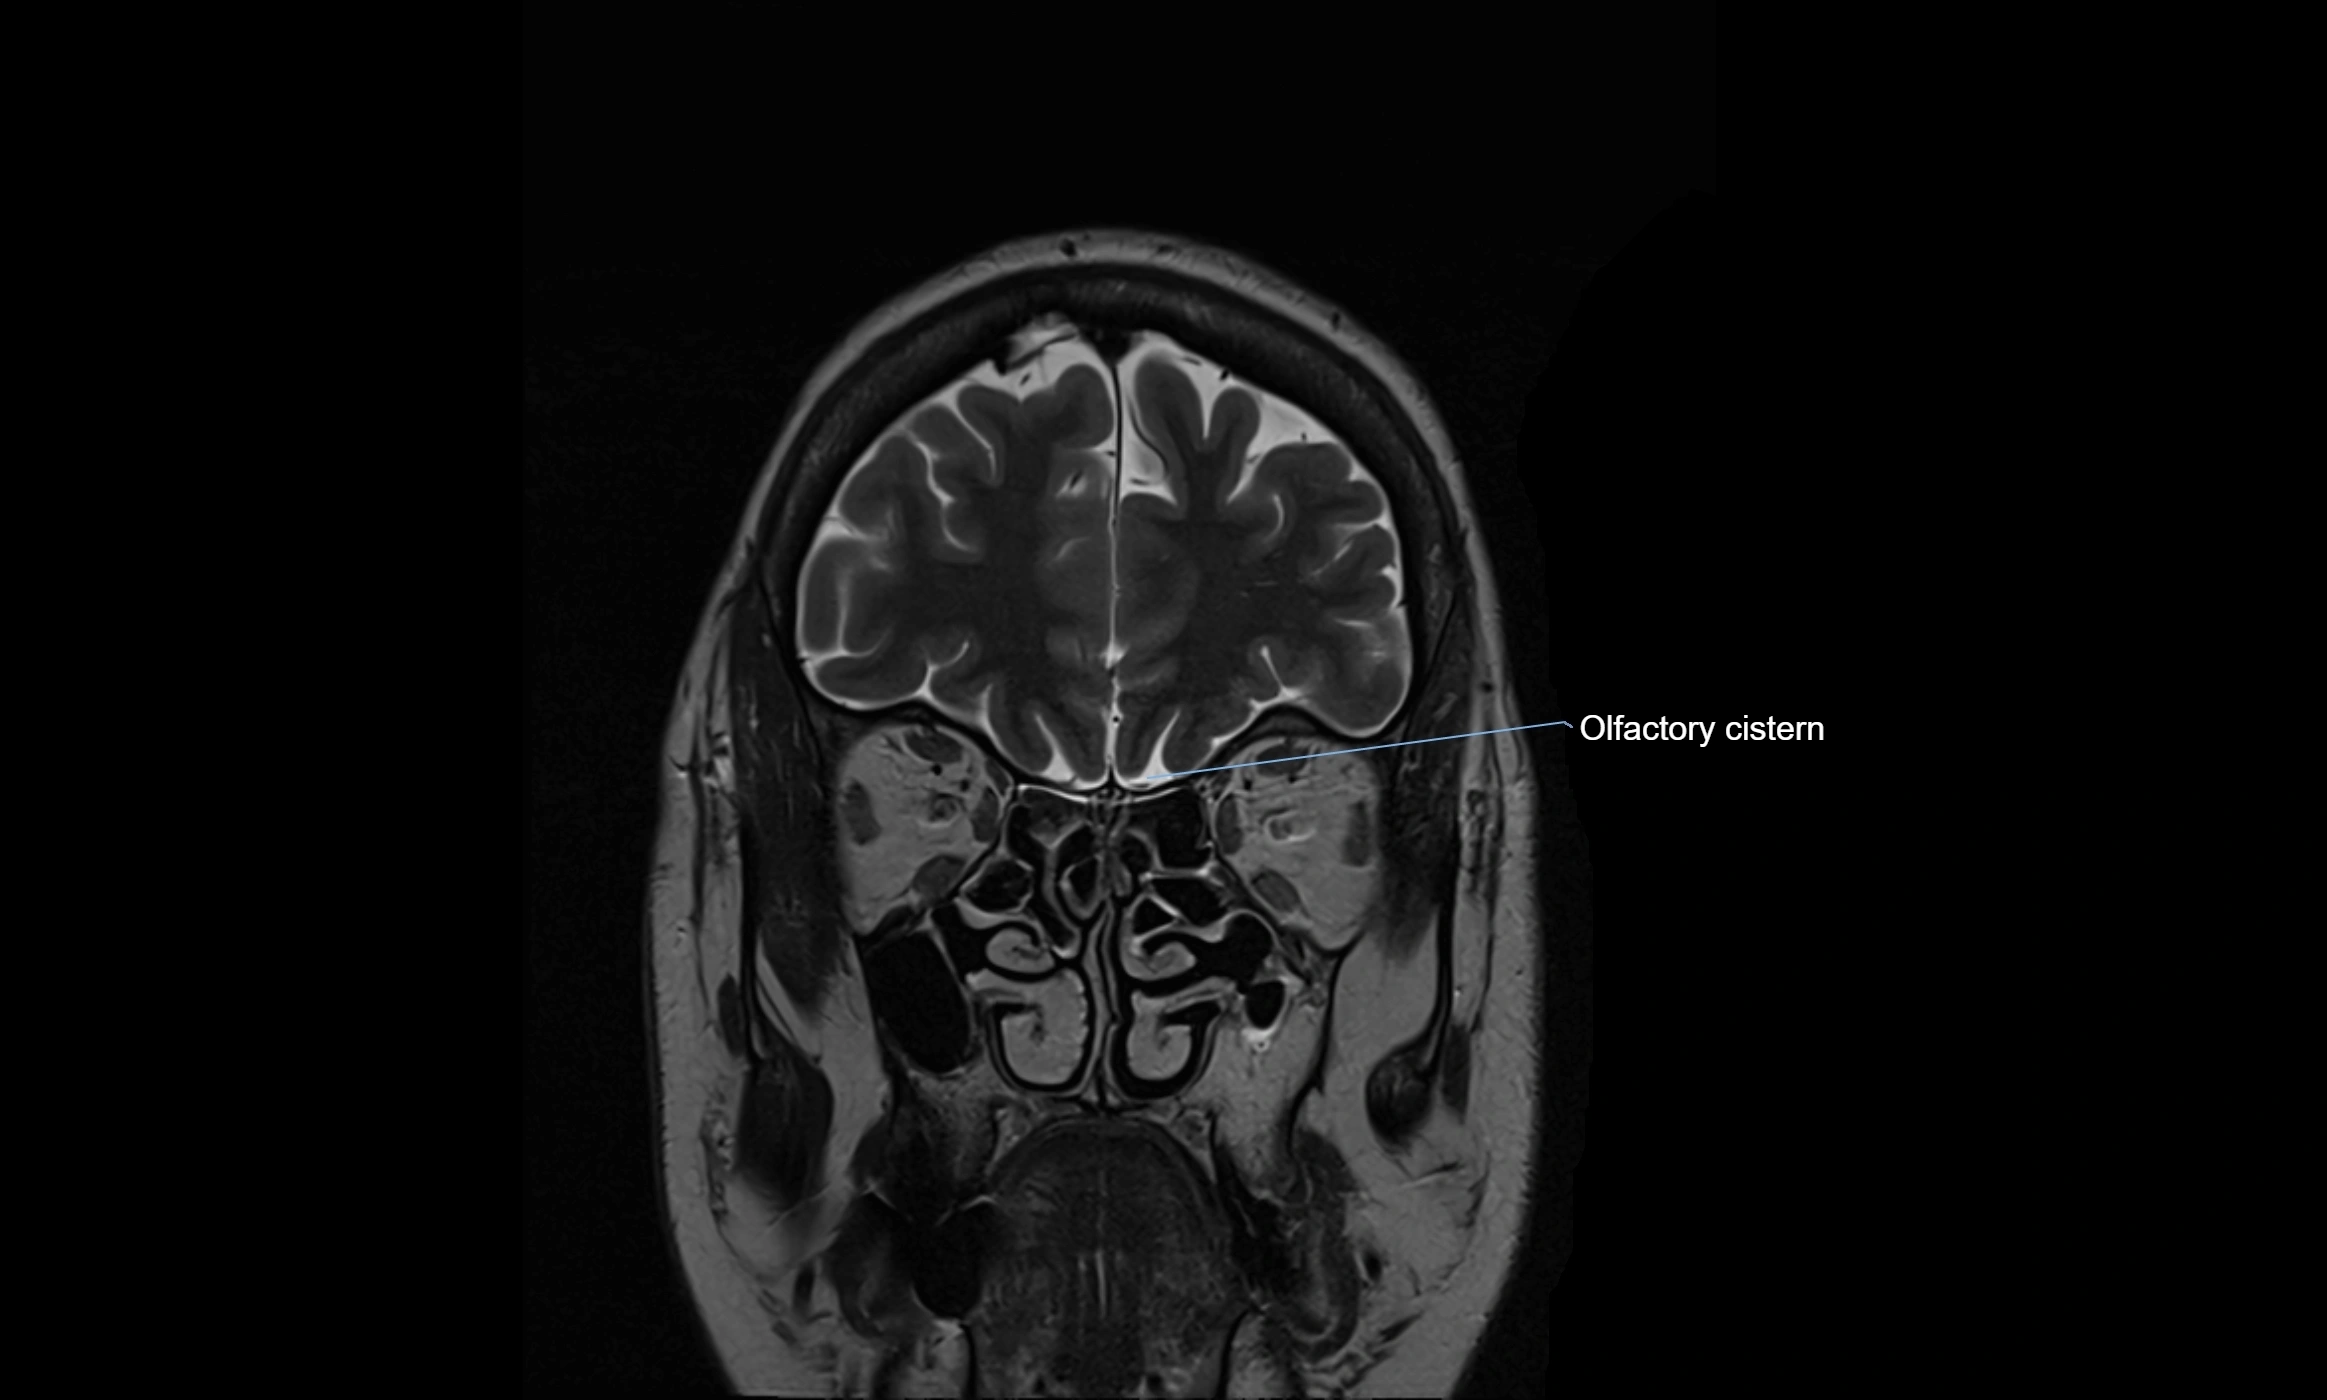

MRI images

image